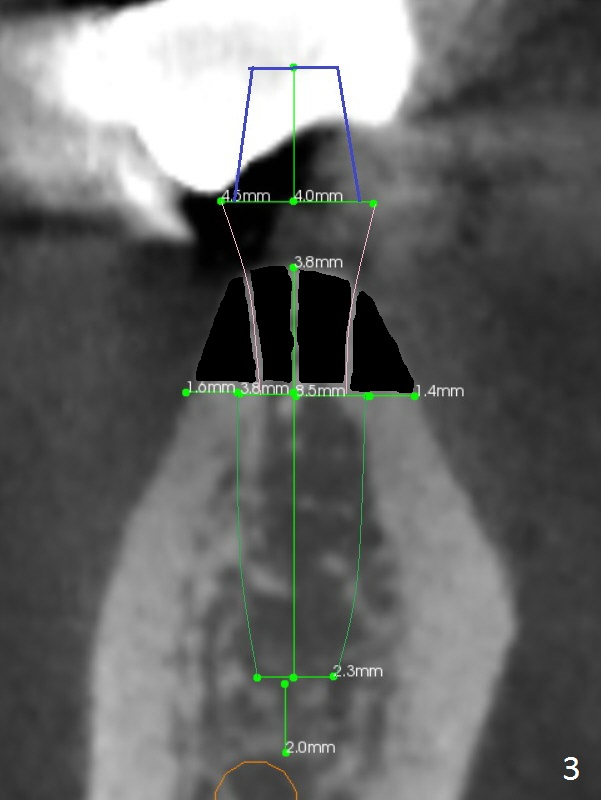

The ridge at #30 is pointed (Fig.2) and going to be resected (Fig.3 black area) to receive a narrow, short implant (3.8x8.5 mm). A splinted immediate provisional will be fabricated following placement of a 4.5x4(5) mm abutment at #30 (Fig.2,3). Take Alginate impression when the patient arrives in case the tooth #31 is also non-salvageable.